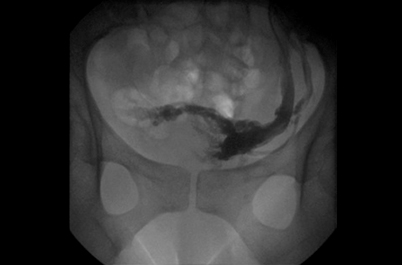

Fig. 1: Examen con Doppler color por vía transvaginal, demostrando dilatación de las venas utero ováricas del lado izquierdo.

Hallazgos imagenológicos. En el eco Doppler ginecológico por vía transvaginal se observa varicocele pelviano (Fig. 1). La vena ovárica derecha mide 3.8 mm, y la izquierda, ectásica, 7.4 mm (Fig. 2). En el eco Doppler abdominal se visualiza la vena renal izquierda, de 3.1 mm en topografía del compás aorto-mesentérico y 8.1 mm en el segmento proximal al riñón izquierdo, con una velocidad 50cm/s en el compas y 30cm/s en el segmento proximal al riñón. El estudio corresponde en primera instancia a un síndrome de Nutcracker (Fig. 3).